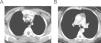

Utilidad de la tomografía computarizada y de la resonancia magnética en el diagnóstico de la arteritis de takayasu

Usefulness of computed tomography and magnetic resonance imaging in the diagnosis of Takayasu's arteritis